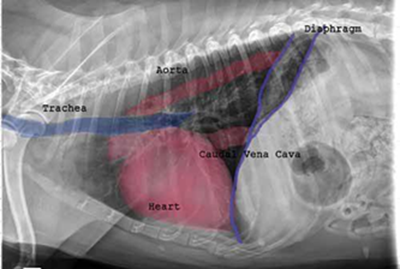

Radiography (x-ray) is used to determine if the heart is enlarged

(particularly the left atrium and left ventricle), if the veins from the

lungs to the heart are distended, or if fluid is beginning to develop in the

lungs.* X-rays also will show any enlargement of

the pulmonary vein, a classic symptom of congestive heart failure (CHF).

As noted above, what is not visible outwardly, before the dog reaches heart failure, is enlargement of the left chambers of the heart. As greater quantities of blood leak through the damaged mitral valve from the left ventricle back into the left atrium, the thin-walled atrium gradually begins to swell and enlarge (see x-ray image of a severely enlarged left atrium, outlined in red, above) -- called remodeling or cardiomegaly or dilation -- to accommodate the overload of blood, and there is a reduction in the ability of the left ventricle to provide sufficient blood to meet the demands of the rest of the body. The heart then has to pump harder and faster, to meet those demands. The shut-down of the distant blood vessels also has the effect of causing the left ventricle to beat against a higher resistance, causing another increase in mitral valve leakage.